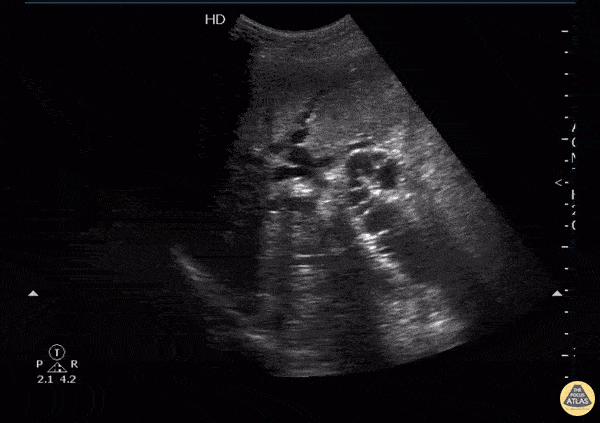

Biliary - Dilated cystic duct and spiral valves of Heister

Patient originally presented with right upper quadrant to mid epigastric pain with jaundice. An obstructing mass can be seen at the head of the pancreas along with intra-heaptic and extra-hepatic duct dilation. The “candy cane” appearing structure is the dilated cystic duct with spiral valves of Heister visible. Image courtesy of Robert Jones DO, FACEP @RJonesSonoEM Director, Emergency Ultrasound; MetroHealth Medical Center; Professor, Case Western Reserve Medical School, Cleveland, OH View his original post here